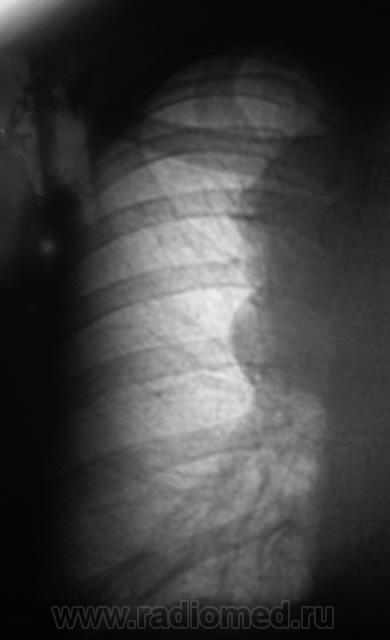

Произвели томограмму в боковой проекции.

Приложения:

21..l..JPG22..l.jpg23..l..JPG24..l..jpg